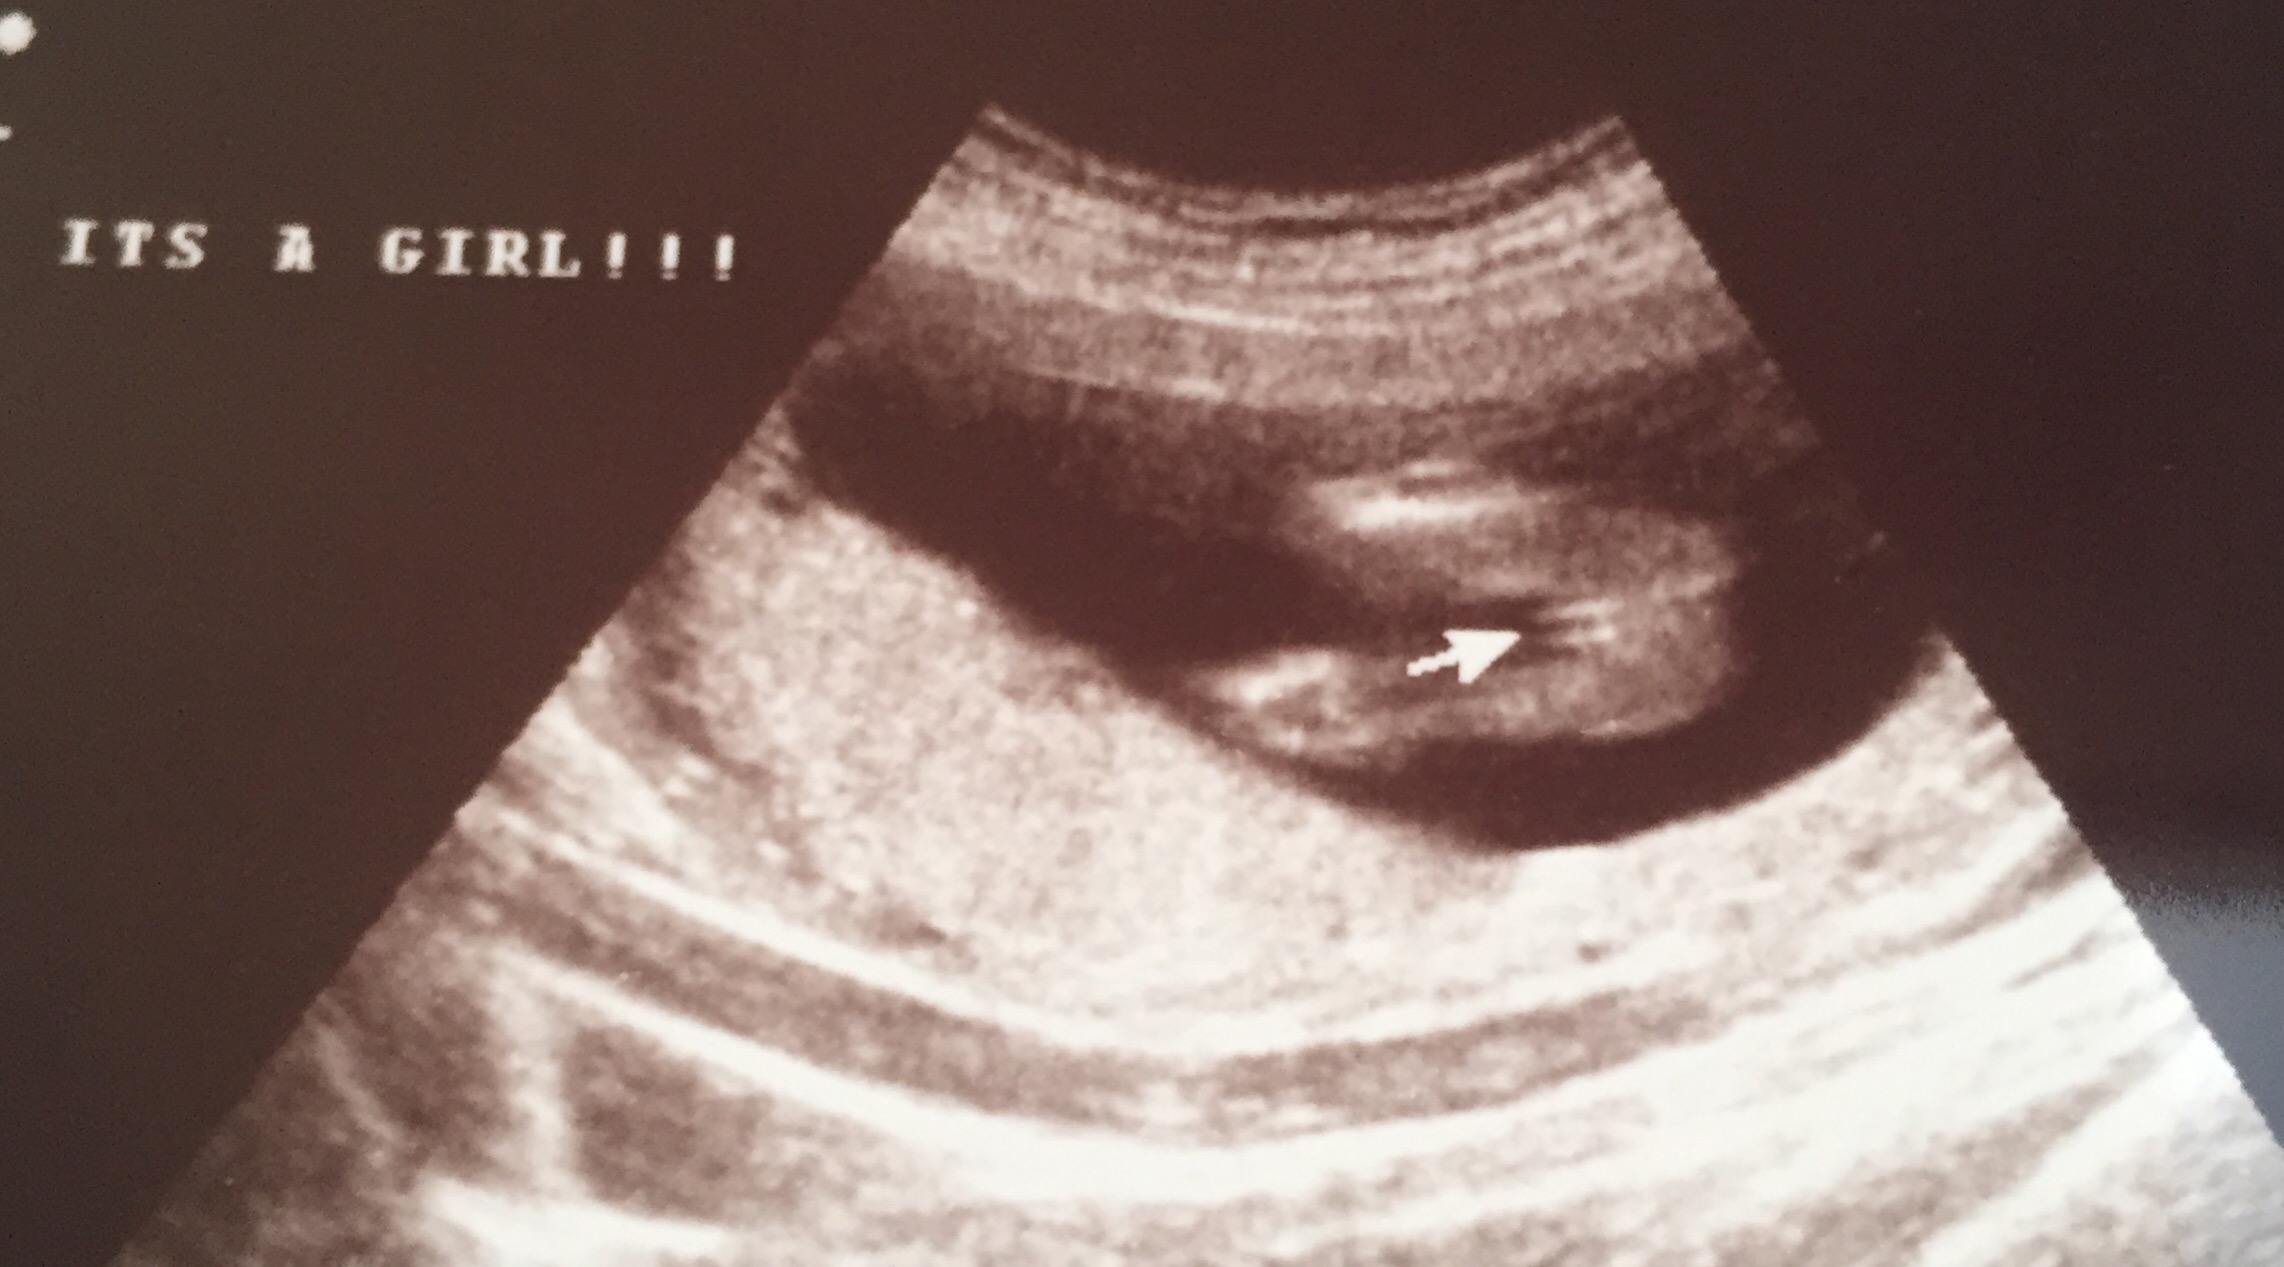

I'm leaning girl, did you have any other pictures at all? here is mine from 18 weeks I know its a little further on but it gives you a rough idea something to compare to :)

Attachment 39232